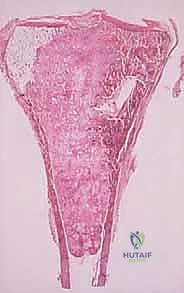

هنا تبرز أهمية الخزعة؛ فالتصوير الإشعاعي مهما كان متقدماً لا يمكنه تأكيد نوع الخلايا بنسبة 100%. التقييم النسيجي تحت المجهر هو الدليل القاطع الوحيد.

قراءة تقرير علم الأمراض (الباثولوجي): ماذا بعد الخزعة؟

تستغرق نتائج الخزعة عادة من أسبوع إلى أسبوعين. هذه الفترة قد تكون مليئة بالقلق للمريض وعائلته، ولكنها ضرورية لقيام طبيب علم الأمراض (Pathologist) بفحص الخلايا تحت المجهر وإجراء صبغات مناعية كيميائية (Immunohistochemistry) لتحديد النوع الدقيق للورم.

بمجرد صدور التقرير، يقوم الأستاذ الدكتور محمد هطيف بمناقشة النتائج بشفافية وأمانة طبية تامة مع المريض.

- إذا كان الورم حميداً: قد يكتفي بالمراقبة الدورية، أو يوصي باستئصال بسيط إذا كان الورم يسبب ألماً أو يهدد بكسر العظم.

- إذا كان الورم خبيثاً (ساركوما): يتم وضع خطة علاجية شاملة (Multidisciplinary approach) قد تتضمن العلاج الكيميائي، العلاج الإشعاعي، والجراحة الكبرى لاستئصال الورم مع الحفاظ على الطرف (Limb Salvage Surgery).